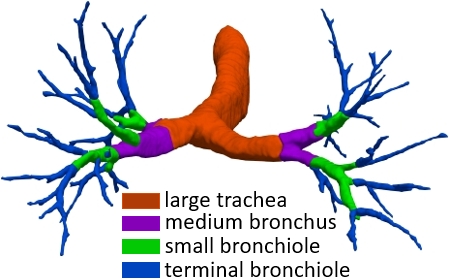

Ablation studies. To verify the efficacy of each module, we perform the thorough ablation studies in supplementary Tables 3-5 and Figs. 7-8. In Table 3, the 2-th row on lung fibrosis dataset with the proposed FA-based transformer-like backbone achieves the largest 2.24% CCFs, verifying the efficacy of fusing fuzzy sets and deep network to diminish the uncertainty in feature representations significantly. The 3-th row with GLCF module indicates 1.02% CCFs, proving that we only need to focus much on the very hard BVP rather than all regular dense points, which provide the most important losing information of discontinuity or details in the network down-sample operation. Since we only extract the BVP to render, it can suppress the redundant background to further solve the severe class imbalance issue of foreground and background voxels. Supplementary Table 4 evidences the efficacy of GLCF module which improves the border accuracy obviously by 4.72%. In Table 5, the 2-th row with FA-based transformer-like backbone improves the DBR significantly on the terminal (1.8%), small (1.25%) and medium (1.65%) branches except the large trachea (-1.03%), for most uncertainty in the feature representations is from the terminal, small and medium branches that are too thin and hard to be discerned while annotating. The 3-th row with GLCF module realizes the significant promotion of DBR on the small (2.02%), medium (2.02%) and large (3.09%) branches, which is consistent with Fig. 8 to overcome the issue of detail loss in the network down-sample operation and render the BVP effectively. Supplementary Fig. 7 elucidates that our FA-based transformer-like backbone can enhance the feature representations of lung organs significantly.